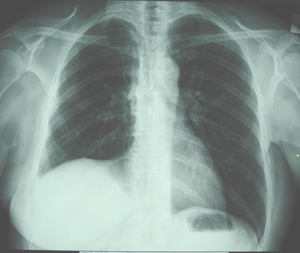

Εικόνα 4

Οπισθιο-πρόσθια ακτινογραφία θώρακος μετά από δεξιά θωρακοτομή-άνω λοβεκτομή. Πλήρης έκπτυξη του μέσου και του κάτω λοβού.